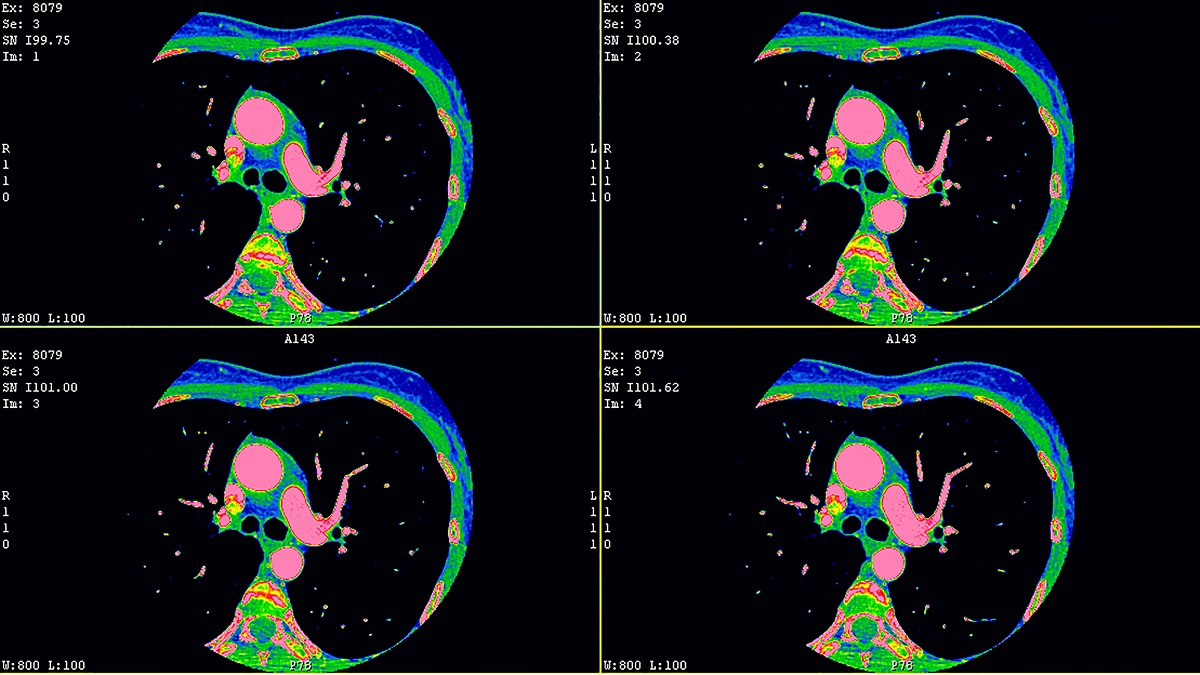

Echo Imaging

This area is dedicated to the in-depth study of 2D/3D transesophageal and intracardiac echocardiography, with a focus on perioperative and interventional imaging of heart valve diseases.

The meetings combine theoretical lectures based on ESC guidelines with practical sessions, including hands-on workshops and wet-labs on porcine hearts, aimed at developing advanced skills in 3D dataset acquisition and analysis, as well as the use of intracardiac echocardiography.